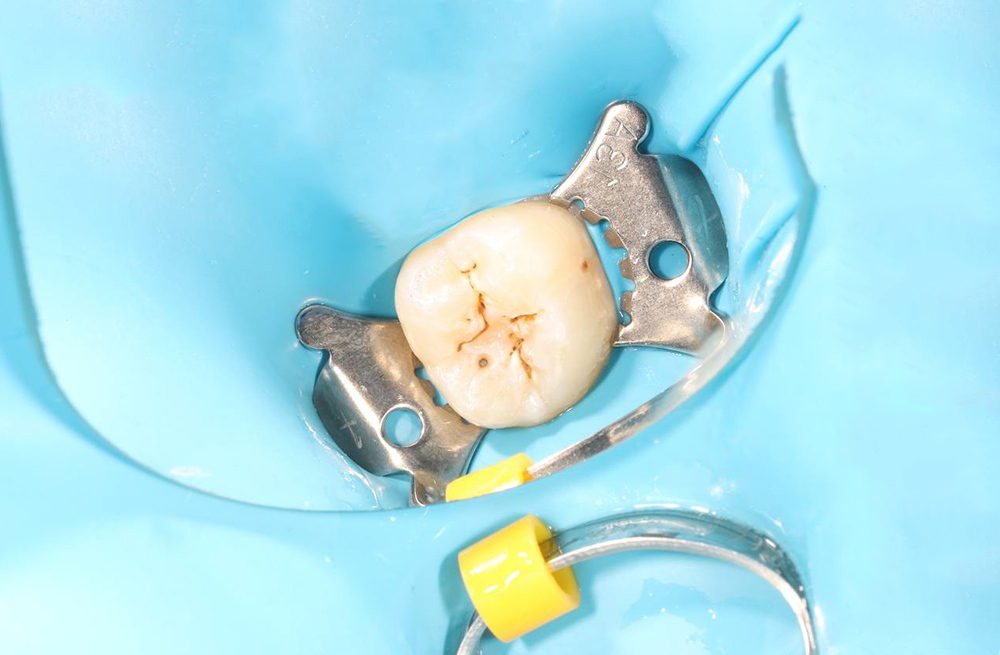

Устранение кариозного поражения зуба с применением коффердама и композитной реставрации